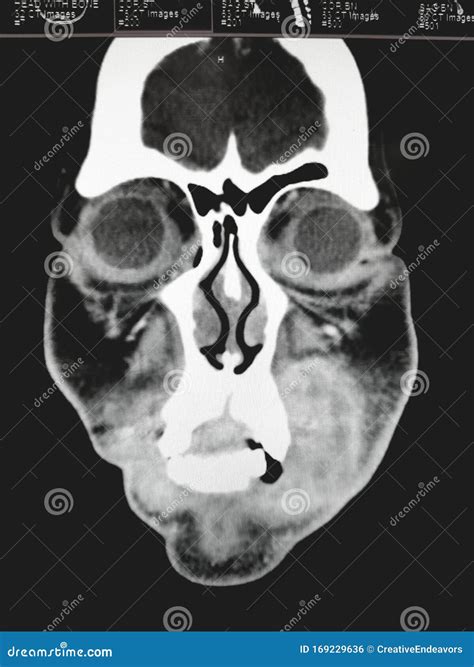

A computed tomography (CT) scan is a sophisticated imaging technique that uses X-ray technology coupled with computer processing to create highly detailed, multi-dimensional images of the body. When specifically applied to the sinuses—often referred to as a paranasal sinus CT—the procedure captures images of the air-filled cavities located around the nose and eyes.

Unlike standard X-rays, which may offer a limited view, a Ct scan sinus evaluation provides a "slice-by-slice" perspective. This allows an Ear, Nose, and Throat (ENT) specialist to detect subtle abnormalities that might be hidden during a routine physical examination. It helps in distinguishing between simple inflammation, polyps, fungal infections, or structural issues like a deviated septum.

Once the images are captured, they are processed by a radiologist. The radiologist looks for specific markers of health or disease. They will examine the sinus ostia (the small openings where sinuses drain) to see if they are blocked by polyps or mucosal swelling. They will also look for opacification—a term used when the typically air-filled sinuses appear white or gray on the image, indicating they are filled with fluid, mucus, or thickened tissue.